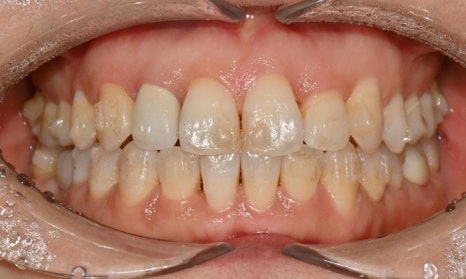

어태치먼트 주변의 착색 및 변색

첫번째 사진은 인비절라인 치료 중인 환자분 사진으로, 어태치먼트 주변으로 착색도 발생한 것을 확인할 수 있습니다. 두번째 사진은 어렸을 때 해외에서 인비절라인을 하다가 어태치먼트를 제거하지 않고 오래 유지를 하다가 내원해서 마무리 교정을 하기 위해 저희 병원에 내원한 환자 사진으로, 어태치먼트 주변이 노랗게 변색된 것을 확인할 수 있습니다.